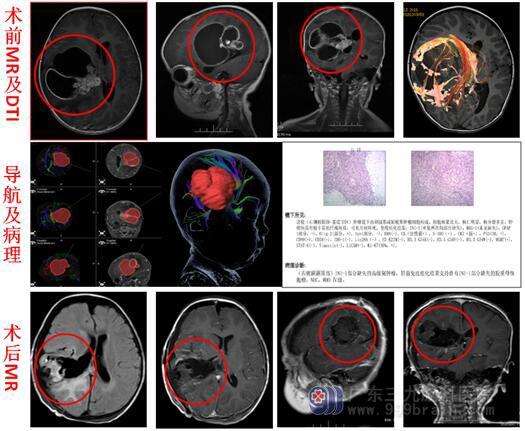

入住综合神经外科,进一步头颅MRI显示:1.右侧颞叶-丘脑巨大占位性病变,范围约为7.2cm×7.5cm×7.3cm,考虑为恶性肿瘤,胚胎性肿瘤或间变室管膜瘤可能,并可疑脑脊液播散转移;2.右侧大脑镰下疝形成;右侧海马钩回疝形成。

家属积极地要求手术治疗,由鲁明副院长主刀,在全麻下行“右侧额颞顶部基底节区占位病变切除术”,术中见肿瘤囊变组织,有淡黄色囊液流出,切除囊壁,深部见病变实质组织,呈灰褐色,质软,边界不清,血供丰富,予显微镜下分块切除,手术顺利。术后病理:胶质母细胞瘤,WHO IV级。